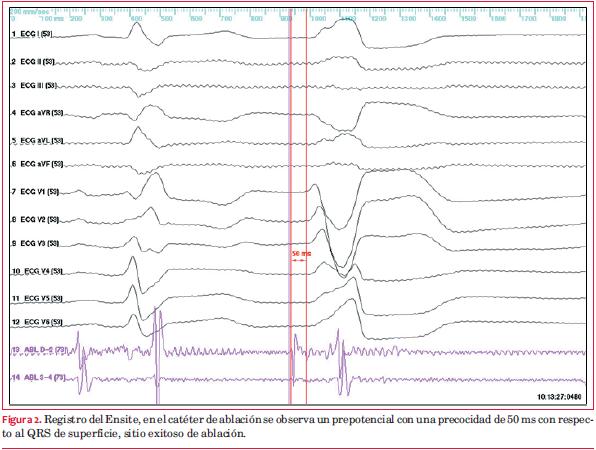

Se posiciona el catéter balón a nivel de tracto de salida del ventrículo derecho (TSVD). Con catéter irrigado se realiza reconstrucción anatómica del TSVD y posteriormente se realizó cartografía sin contacto de la extrasístole (figura 3). Se topografía el foco de origen sobre el anillo tricuspídeo sector superior entre la hora 1 y 2 en proyección oblicua anterior izquierda y considerando la válvula tricúspide como un reloj. A 1 cm del registro de potencial de His. La precocidad conseguida en registro unipolar fue de 50 ms con respecto al inicio del QRS (figura 2). Se aplica radiofrecuencia con catéter irrigado (40 Watts, 55 grados y 60 segundos), desaparece la arritmia a los 3 segundos de iniciada la aplicación (figura 4).